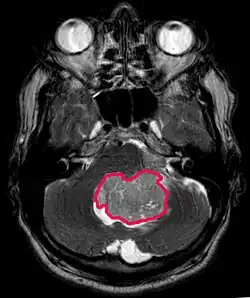

Cette tumeur est typique de la fosse postérieure, où elle est localisée dans les deux hémisphères du cervelet ou dans le vermis cérébelleux. Parce qu'il est envahissant et à croissance rapide, il se propage généralement à d'autres parties du système nerveux central (SNC) via le LCR et peut infiltrer le plancher du quatrième ventricule voisin et les méninges. Plus rarement, des métastases supplémentaires du SNC peuvent survenir. Lorsque la tumeur maligne survient, les symptômes comprennent la perte d'équilibre, l'incoordination, la diplopie, la dysarthrie et l'atteinte du quatrième ventricule, ce qui entraîne souvent une hydrocéphalie obstructive, des maux de tête, des nausées et des vomissements et une démarche instable.

L'IRM montre généralement une lésion de contraste massive impliquant le cervelet. Comme mentionné ci-dessus, le médulloblastome a une forte propension à infiltrer localement les leptoméninges ainsi qu'à se propager à travers l'espace sous-arachnoïdien, impliquant les ventricules, la convexité cérébrale et les surfaces leptoméningées de la colonne vertébrale. Par conséquent, il est nécessaire de mettre en résonance tout l'axe crânio-spinal.

Le but de la chirurgie est d'enlever autant que possible la masse présentée par la lésion. En effet, les tumeurs résiduelles postopératoires entraînent un moins bon pronostic. La présence de cellules tumorales dans le liquide céphalo-rachidien ou la détection par résonance de métastases leptoméningées est également un signe avant-coureur d'un pronostic défavorable. La chirurgie seule n'est généralement pas curative. Dans certains cas, cependant, une irradiation thérapeutique de l'axe craniospinal, focalisée sur le site tumoral primaire, peut en résulter. L'ajout d'une chimiothérapie après la radiothérapie augmente le taux de guérison. Des médicaments à base de platine (cisplatine ou carboplatine), de l'étoposide et un agent alkylant (cyclophosphamide ou lomustine) sont utilisés avec la vincristine. Avec un traitement approprié, les cas de longue survie de plus de 3 ans chez les patients atteints de médulloblastome varient de 60 à 60 ans et 80 Pour cent.